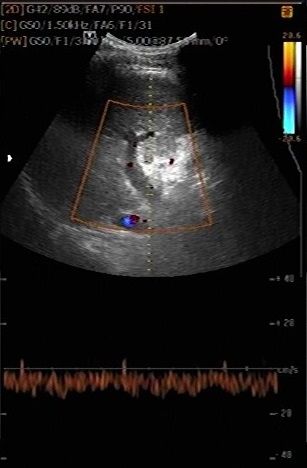

Image d'une

thrombus de la veine porte . Cirrhose du foie |